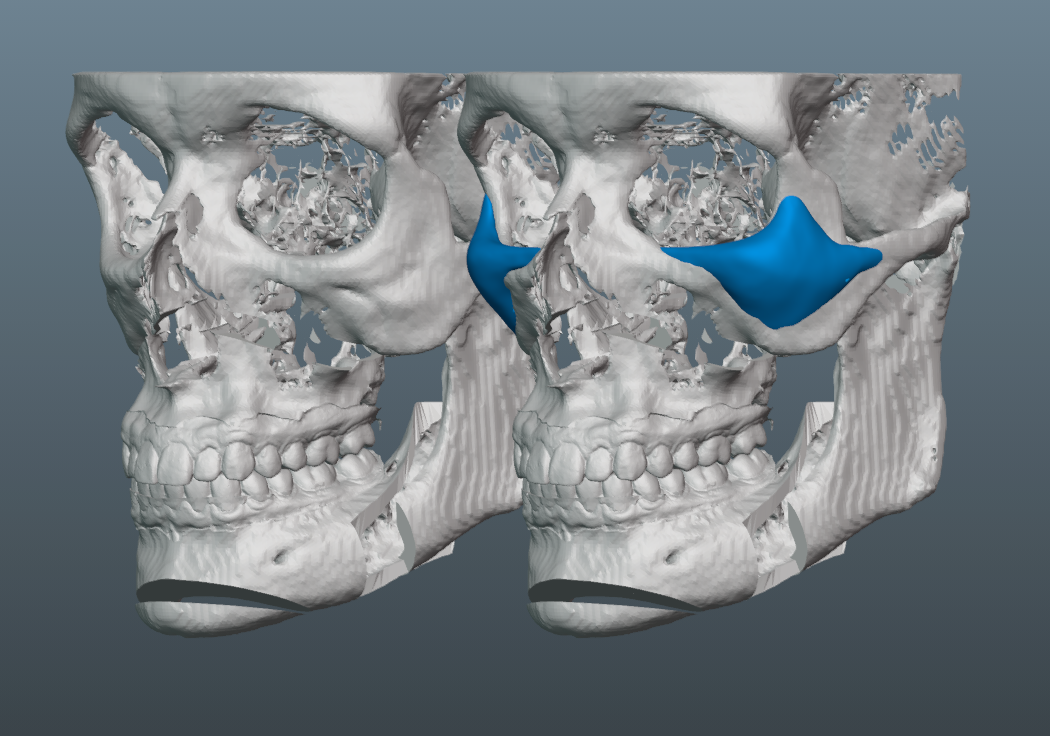

Trimax with around 7mm forward movement and 4mm downgraft.

Needed a lot of projection on the malar part of the implant, since the patient has a fairly flat midface, which would have been exacerbated by the bimax.

-6mm malar projection.

-3mm saddle on the infras.

-Minimal projection on medial part of infra region. This helped keep the taper minimal and avoids too much of the infamous infra implant shelfing/step-off.

-Though we initially tried to do a smaller implant, it became clear that it was necessary to increase its size, so that we could ensure better transitions to the submalar region, zygo arch and lateral orbital rim.